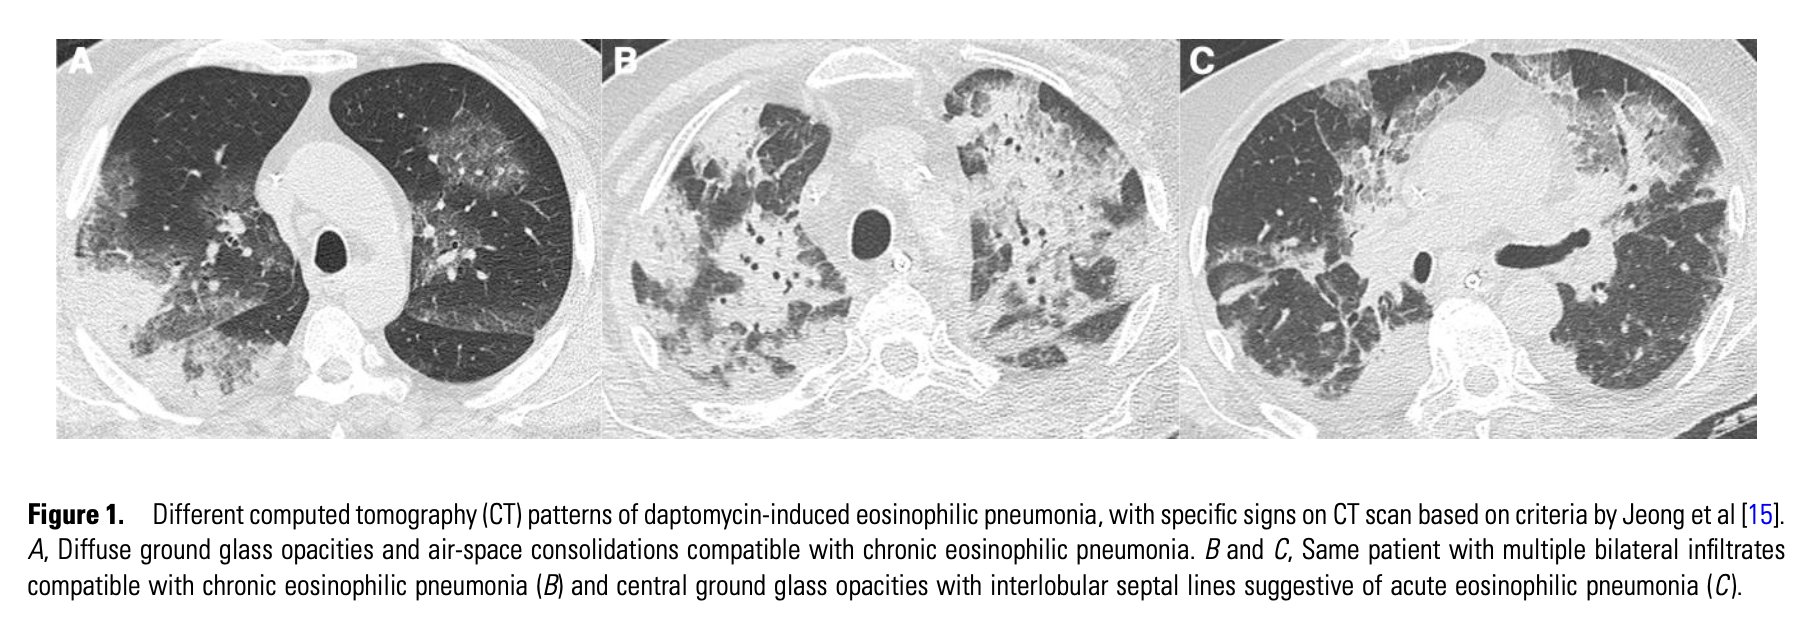

画像所見

49例を含むシリーズでは、胸膜下に多発する網状結節性浸潤影すりガラス陰影を伴うびまん性の両肺浸潤影など慢性好酸球性肺炎の一致する所見が認められた。しかし、急性好酸球性肺炎の特徴である胸水貯留も3分の2の症例で認められた。

74症例の最近のシステマティックレビューでは、43例にBALが行われ、好酸球数の中央値は20.5%(IQR 10.5-20.5、幅 0-98%)だった。両側の浸潤影が68.1%、すりガラス陰影が41.7%、斑状の浸潤影が30.6%、末梢優位の陰影を19.4%に認めた。ダプトマイシンの投与量は中央値6mg/kg(IQR 6.0-7.9)。症状はダプトマイシン投与開始から中央値19日(IQR 12-24)で出現した。末梢血の好酸球上昇は86.5%に認めた。治療はダプトマイシン中止のみが27%、投与中止かつグルココルチコイド投与は51.4%であった。96時間以内に87%の患者が改善を認めた。